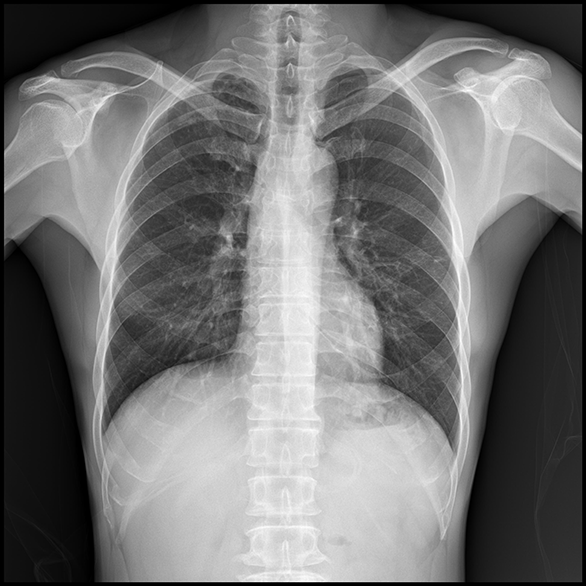

La serie EVS Advanced proporciona una excelente experiencia de imagen en reducción de dosis y claridad diagnóstica.

EXPRIMER Advanced Series proporciona una alta calidad de imagen con un 50 % menos de dosis que CR y un 25 % o más de dosis reducida en comparación con DR.

La dosis reducida para el paciente se logra a través del potente rendimiento de dosis baja de EXPRIMER Advanced Series.